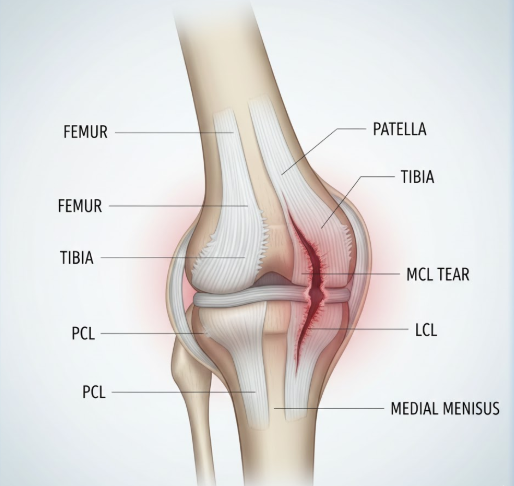

2) 무릎 안쪽 통증의 원인

- 내측 측부인대 손상

- 무릎 안쪽 통증의 대표적 원인

- 무릎이 바깥쪽으로 꺾이는 외력을 받을 때 안쪽 인대가 늘어나거나 찢어짐

- 걸을 때 안쪽에 찌르는 듯한 통증 발생

- 무릎이 불안정하게 느껴짐

- 외측 측부인대 손상

- 무릎이 안쪽으로 꺾일 때 바깥쪽 인대 손상으로 발생

- 내측 인대 손상보다는 덜 흔함